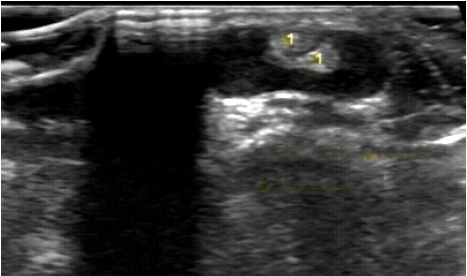

Na imagem, está representada uma tenossinovite do compartimento I (De Quervain). Os tendões deste compartimento são:

Enunciado 1328859-1